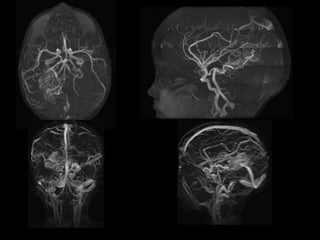

RNM CEREBRAL

20-06-2023.

RMN DE CRÁNEO

20/06/2023

ADQUISICIÓN AXIAL

T1 T2 FLAIR

DWI ADC EG

ADQUISICIÓN AXIAL.

T1 CC

ANGIO TOF

3D

 Malformación arterio-venosa cerebral con

dilatación aneurismática de la vena de galeno vs

aneurisma de la vena de galeno vs fístula

arteriovenosa pial. Escala de Spetzler – Martin 5

puntos.

 Pansinusopatía.

 Hipertrofia turbinal.

CONCLUSIONES:

ADQUISICIÓN AXIAL T1 T2FLAIR DWI ADC EG

 Malformación arterio-venosacerebral con dilatación aneurismática de la vena de galeno vs aneurisma de la vena de galeno vs fístula arteriovenosa pial. Escala de Spetzler – Martin 5 puntos.  Pansinusopatía.  Hipertrofia turbinal. CONCLUSIONES: